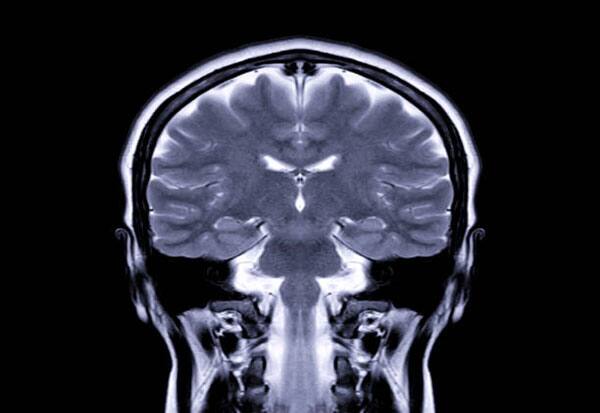

The amygdala, located deep within the brain, is a small, almond-shaped structure and plays a central role in processing and regulating emotions.

The basolateral amygdala helps process the emotional part of information received via senses.

People with Urbach-Wiethe Disease differ in their emotional and social behaviour. The condition is known to selectively damage the basolateral amygdala without affecting other brain regions.